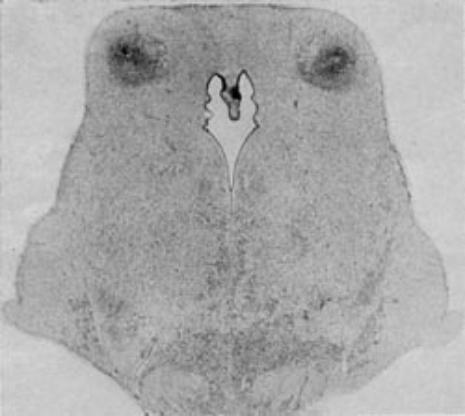

Figure 4:  Damage of the

inferior colliculi: Result of

subjecting a newborn

monkey to 12 minutes of

total asphyxia.

(from Myers 1972)